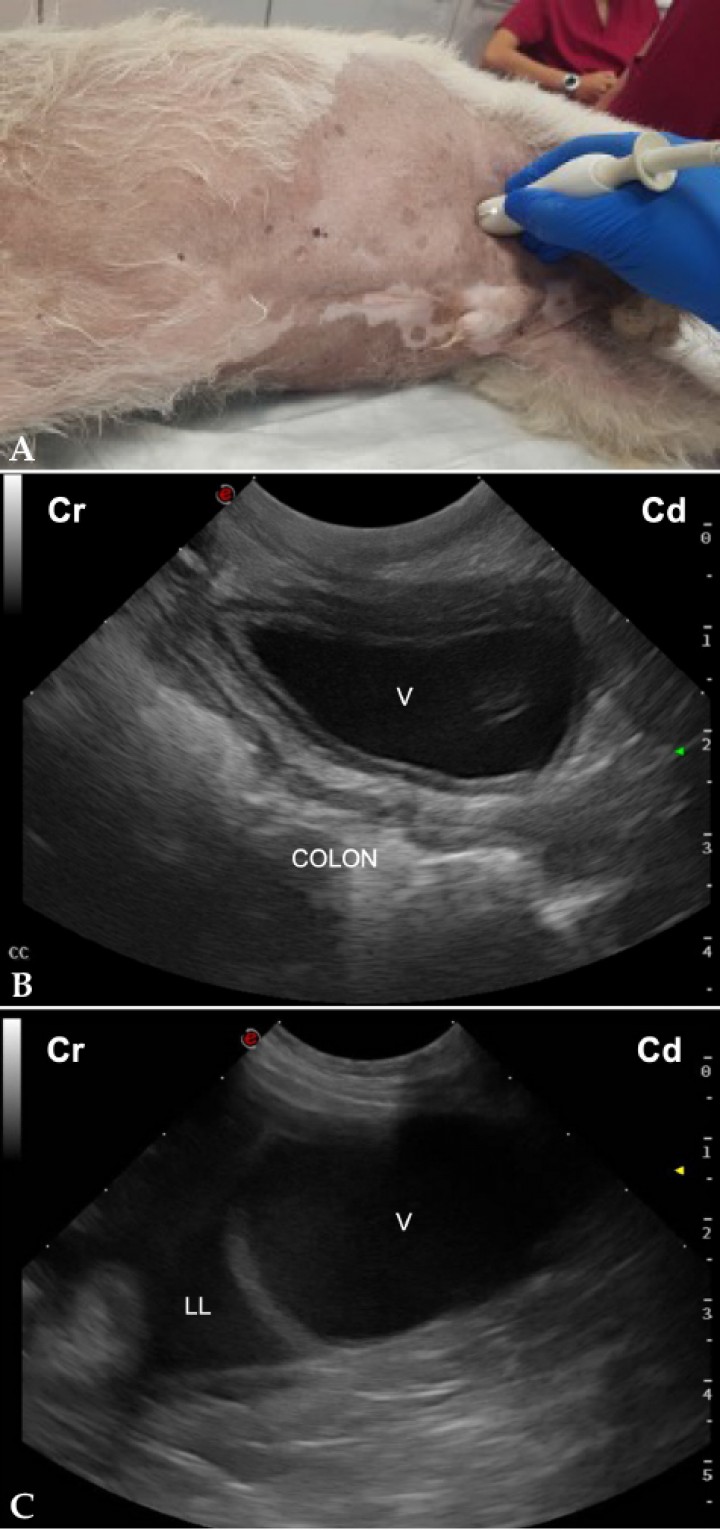

- Vista caudal (Fig. 3A): Permite un chequeo del área cistocólica (CC), evaluando el aspecto más craneal de la vejiga en una vista longitudinal de la misma (Figs. 3B y 3C).[ Boysen SR, Lisciandro GR: The Use of ultrasound for dogs and cats in the emergency room. AFAST and TFAST. Vet Clin Small Anim 2013; 43: 773-797. [PubMed] , Lisciandro GR: The abdominal FAST (AFAST) exam. En Lisciandro GR (ed): Focused ultrasound techniques for the small animal practitioner, Oxford, Wiley Blackwell, 2014; 17-43. , Kinns J: Abdomen. En Barr F, Gaschen L (ed): BSAVA Manual of canine and feline ultrasonography, Gloucester, BSAVA, 2011; 72-84. ]

<p>(<strong>A</strong>) Posicionamiento de la sonda de ecografía para obtener la vista caudal. (<strong>B</strong>) Imagen ecográfica del área cistocólica (CC) de un perro sano, en la que se observa la vejiga (V) y el colon en corte longitudinal. Cr: craneal; Cd: caudal. (<strong>C</strong>) Imagen ecográfica del área cistocólica (CC) de un perro con hemoabdomen, en la que se observa la presencia de líquido libre anecogénico (LL) cranealmente a la vejiga (V). Cr: craneal; Cd: caudal.</p>

Figura 3

(A) Posicionamiento de la sonda de ecografía para obtener la vista caudal. (B) Imagen ecográfica del área cistocólica (CC) de un perro sano, en la que se observa la vejiga (V) y el colon en corte longitudinal. Cr: craneal; Cd: caudal. (C) Imagen ecográfica del área cistocólica (CC) de un perro con hemoabdomen, en la que se observa la presencia de líquido libre anecogénico (LL) cranealmente a la vejiga (V). Cr: craneal; Cd: caudal.